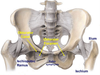

ligament of head of the femur

aka ligamentum teres

pectineus